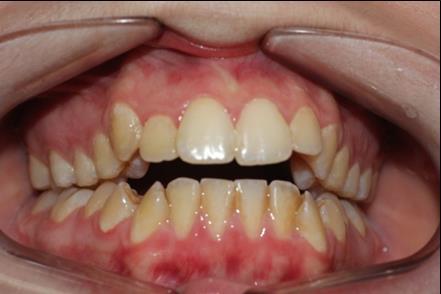

The patient, a 21-year old woman , had a convex profile , class I dental malocclusion ,anterior open bite of 4 mm . She was a mouth breather and presented tongue thrust. Her chief complain was the anterior open bite .(Figure 1)

Figure 1.Pretreatment intraoral photography

Pretreatment intraoral photography